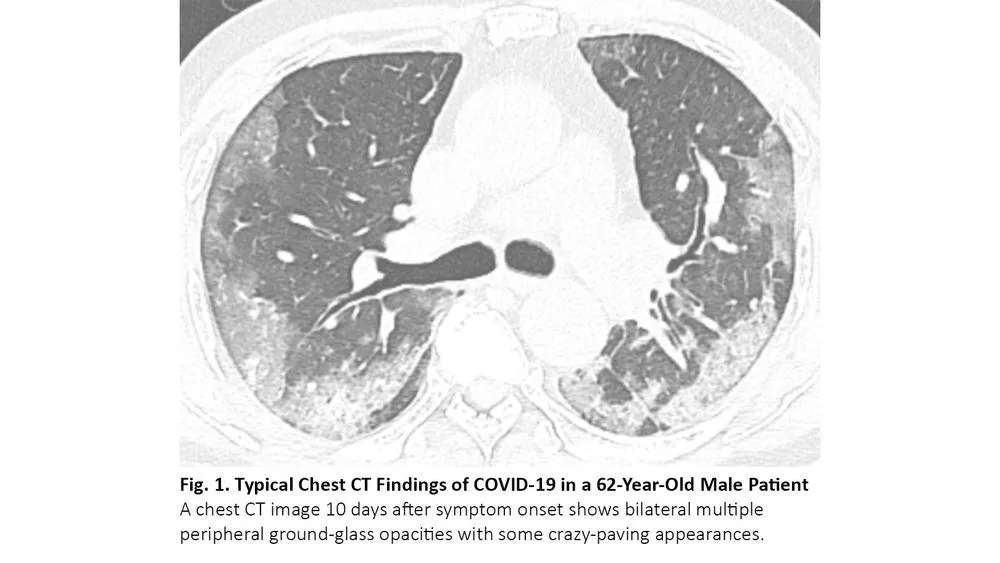

COVID-19感染者的胸部CT表现

COVID-19患者的肺部CT的典型表现为双侧多发磨玻璃样影,好发于肺周3(图1)。61%~72%的COVID-19患者在症状出现后1周左右有典型CT表现,而非COVID-19患者只有不到10%人群有此类表现。4,5

图1. COVID-19患者胸部CT的典型表现